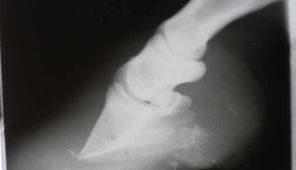

Hufrehe

Die schlimmste aller Hufkrankheiten...

Keine der Erkrankungen bereitet den Pferdebesitzern so viele Sorgen wie die Hufrehe. Obwohl die Symptome generell bei allen Pferden ähnlich sind, ist der Verlauf bei jedem Pferd anders...